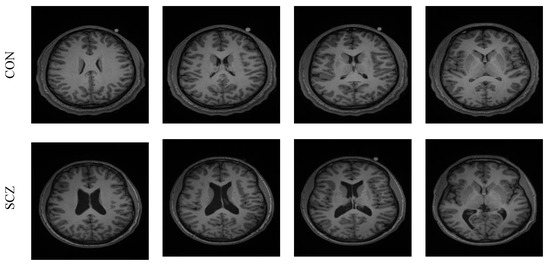

The performance of the developed system was tested and validated using the clinical grade SCZ MRI dataset from [10,11]. This dataset consists of 99 volunteers’ 3D images with the following categories: SCZ, controlled (CON), SCZ-sibling, and CON-sibling. These images were collected from male and female volunteers whose racial demographics included White and African American. The earlier works on this dataset can be found in [21]. In this work, 20 3D MRI images were considered from the CON/SCZ class, and from every volunteer’s 3D data, 30 slices (axial plane) were extracted using ITK-Snap, and every image was then resized to a dimension of 224 × 224 × 3 pixels. The skull section in these images was then eliminated using the thresholding filter/skull stripping algorithm discussed in [22,23]. The test images considered in this work are presented in Table 1 and the sample images are presented in Figure 3.

Figure 3. Sample test images of CON and SCZ class.